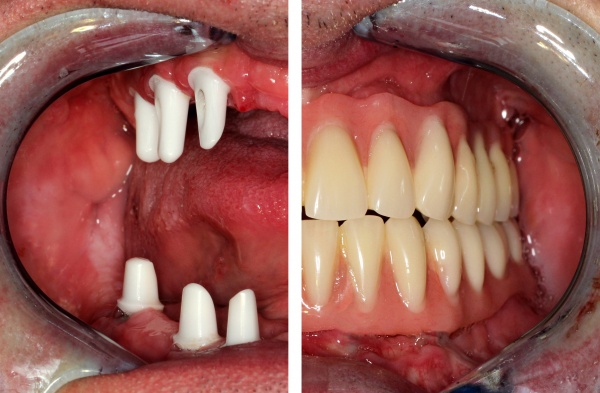

Ein 31jähriger Patient stellte sich am 10.11.2011 in der Implantatsprechstunde vor mit der Bitte um Befürwortung einer implantatgetragenen prothetischen Lösung für eine seit 1997(!) bestehende Schaltlücke 12 bis 22 nach tätlicher Auseinandersetzung.

Die Lücke war bis dato über eine insuffiziente Teilprothese versorgt. Es bestand eine ausgeprägte Oberkieferatrophie in allen Dimensionen mit negativer Stufe im Verhältnis Oberkiefer zu Unterkiefer (Bild) sowie Elongation der Unterkieferfrontzähne (Abb. 9).

Zur Wiederherstellung von Phonetik und Ästhetik und Verhinderung einer weiteren Elongation der Unterkieferzähne wurden für die Rekonstruktion der Oberkieferfront 4 Einzelzahnimplantate beantragt nach vorheriger Augmentation von Beckenkamm.

Zum Ausgleich der konsekutiv vorliegenden Weichgewebsatrophie erfolgte im Juni 2012 nach Genehmigung des Antrags durch das Sanitätsamt der Bundeswehr zunächst die Implantation von 2 Weichgewebsexpandern (Firma Osmed) im Oberkiefer (Abb. 10). Nach Schaffung eines adäquaten Weichgewebsbettes wurde im Juli 2012 zur Korrektur der extremen Hartgewebsatrophie eine Augmentation vom Beckenkamm durchgeführt (Abb. 11). Im Dezember 2012 erfolgten in Lokalanästhesie nach ungestörter Einheilung die Materialentfernung der Osteosyntheseschrauben und die Implantation von 4 dentalen Implantaten (Firma Nobel Biocare, Replace straight, Abb. 12). Durch Atrophie und die rekonstruktiven Operationen bedingt, wurde zur Korrektur der ungenügenden Weichgewebsverhältnisse eine Vestibulumplastik nach 3 Monaten mit Einlagerung einer bioresorbierbaren Membran (Firma Botiss, Mucoderm) durchgeführt. Nach weiteren 3 Monaten erfolgte die Freilegung der Implantate (Abb. 13) mit einer Rolllappenplastik an jedem Implantat zur vestibulären Rekonturierung der Schleimhaut.

Die endgültige prothetische Versorgung erfolgte im Fachzahnärztlichen Zentrum des Bundeswehrkrankenhauses Hamburg auf Patientenwunsch mit 4 verblendeten Nichtedelmetallkronen (Abb. 14). Einer erneuten Weichgewebsplastik zur Konturverbesserung steht der Patient ablehnend gegenüber.